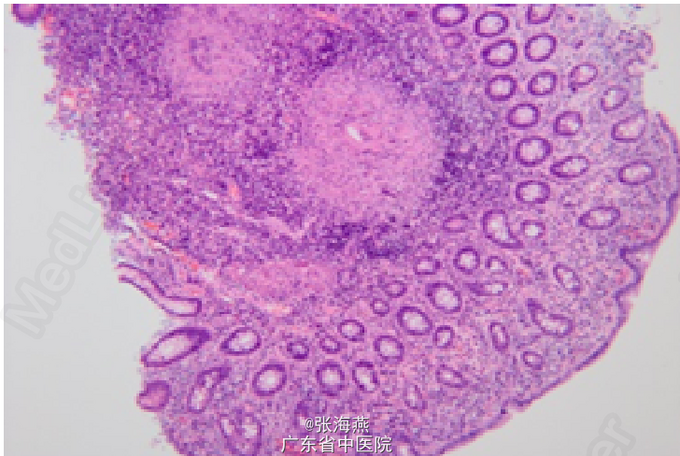

体格检查:T:36.6℃ P:71次/分 R:19次/分 BP:98/58mmHg。腹部查体:腹部软,未扪及包块,右下腹压痛阳性,无反跳痛,余腹部查体无异常,肠鸣音正常。 辅助检查:血常规、输血4项、D二聚体、生化、肝功、心酶、凝血、甲功、免疫6项、CEA、CA199、AFP、尿常规等未见明显异常;粪便常规正常;结核抗体阴性;血沉:29mm/h,C-反应蛋白:12.6mg/L,血脂:TC:3.06mmol/L,HDL-C:0.91mmol/L。胸片、心电图正常。血管炎抗体3项、自免12项未见异常。6月28日行小肠镜检查:、距肛缘约50cm处横结肠、距肛缘约35cm处降结肠可见节段性分布的深大溃疡,被覆白苔,周边粘膜呈息肉样增生,部分呈铺路石样,活检5块送病理。病理示:(升结肠粘膜活检)肠粘膜慢性炎:1.固有膜内慢性炎细胞浸润:重度; 2.中性粒细胞浸润:大量;3.隐窝脓肿:无; 4. 黏膜糜烂溃疡:有;5.隐窝(上皮增生:轻度;不典型增生:无;杯状细胞减少:轻度;潘氏细胞化生:无;腺体萎缩:无)6.炎性息肉形成:无;7.结核样肉芽肿:有。

随访:抗结核疗程结束后及半年末分别复查肠镜,结肠溃疡已完全愈合,肠粘膜散在假性息肉,患者无不适症状。 讨论:肠结核是结核分枝杆菌引起的肠道慢性特异性感染。结核分枝杆菌侵犯肠道主要经口感染,也可血行播散引起,或由腹腔内结核灶直接蔓延引起。单纯的孤立性肠结核临床较为少见。肠结核主要位于回盲部即回盲瓣及其相邻的回肠和结肠。临床主要表现为腹痛、腹块、大便习惯改变、腹泻与便秘交替,并发结核性腹膜炎时,可有发热、腹部压痛、渗出性腹水等。实验室检查可有轻至中度贫血,无并发症时白细胞计数一般正常,血沉多明显增快。结核菌素试验呈强阳性有助于诊断。肠镜上表现为肠壁增生以及粘膜溃疡、粘膜壁水肿、假息肉、管腔狭窄。但这些均非特异性,诊断还要依赖活检。本患者活检发现结核样肉芽肿,肠结核诊断明确。给予规范抗结核治疗后,结肠溃疡愈合。